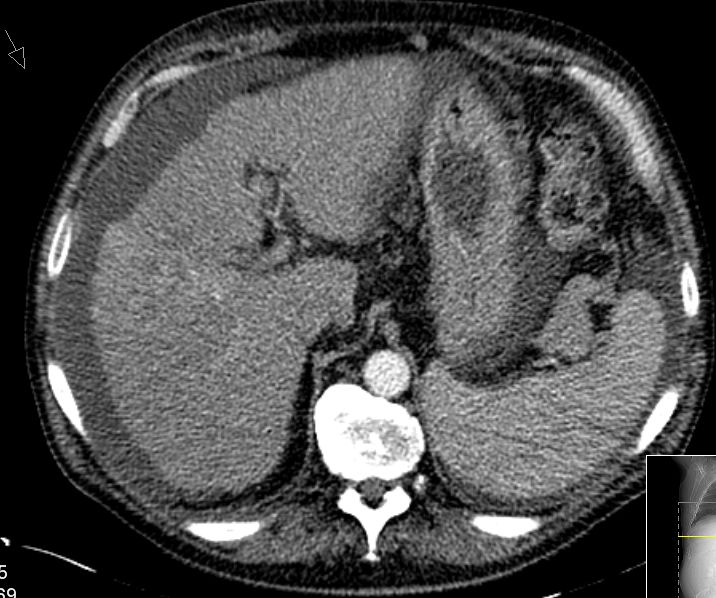

| CT | 61-jähriger trockener Alkoholiker mit bekannter Leberzirrhose und Ascites.

Mehrere Raumforderungen in der Leber. AFP 84. Keine Tumorzellen im Ascites.![]() | ||